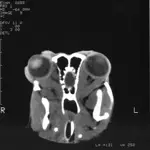

Head CT and extraocular muscle biospy were performed under general anesthesia. Enlargement of the extraocular muscles was apparent OU (Figure 3). No bone lysis, soft tissue mineralization, orbital fractures, foreign bodies, or other abnormalities were detected. Open extraocular muscle biopsy was performed. Dorsal rectus muscle with tendenous insertion (7 mm × 1 mm) was harvested from the lateral one third of the muscle belly.5 Fixed and frozen biopsy sections were submitted for complete muscle profiles. These biopsies showed myofibers and dense

Figure 3. A 43° oblique dorsal plane CT image. This technique was used to optimize extraocular muscle imaging. Abnormalities were limited to bilateral extraocular muscle enlargement.